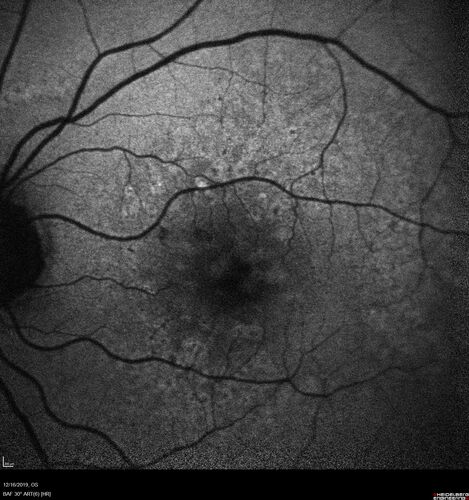

Intermediate Dry Age-Related Macular Degeneration - Soft Drusen

70-year-old Left eye worse than the right.  Both eyes see distortion in the amsler grid for a few months

HTN, High Lipids, Osteoporosis

Meds: Lutein once daily, Calcium, Fish oil, Red Yeast Rice, CoQ10, Magnesium, MVI, Xanax

VA 20/16 OU

2+NS cataract